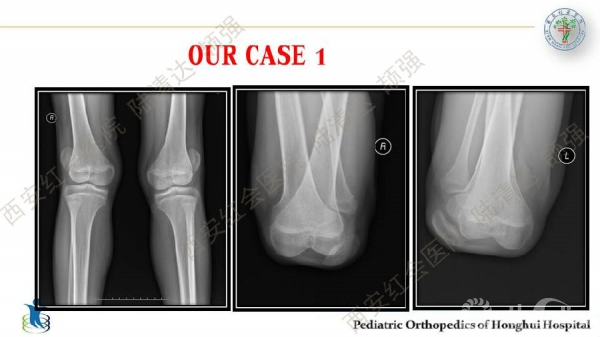

习惯性髌骨脱位,多见于儿童,女性多于男性。临床表现主要为行走步态难看、下肢无力、易摔跤等,而反复摔跤的病史常是患者就诊的主诉。其病理特点主要膝关节内外侧伸肌肌群不平衡及局部结构发育异常,表现为:股外侧肌及膝外侧软组织挛缩,髌韧带附着点偏外,股内侧肌群萎缩无力及MPFL发育不良,髌股关节滑车发育不良及膝外翻畸形等。习惯性髌骨脱位的治疗,建议早发现早治疗。不仅能有效解决脱位问题,还可避免继发畸形。如治疗延误,可出现髋、膝关节继发屈曲、腰前凸加大等畸形。甚至膝关节骨性关节炎,影响工作与生活。